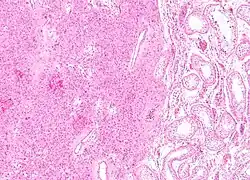

| Micrograph of a granulosa cell tumour, a type of sex-cord–gonadal stromal tumour. H&E stain. | |

Definitive diagnosis of these tumours is based on the histology of tissue obtained in a biopsy or surgical resection. In a retrospective study of 72 cases in children and adolescents, the histology was important to prognosis.[14]

A number of molecules have been proposed as markers for this group of tumours. CD56 may be useful for distinguishing sex cord–stromal tumours from some other types of tumours, although it does not distinguish them from neuroendocrine tumours.[15] Calretinin has also been suggested as a marker.[16] For diagnosis of granulosa cell tumour, inhibin is under investigation. Granulosa cell tumors and Sertoli-Leydig cell tumors have specific genetic mutations that are characteristic and can help support the diagnosis.